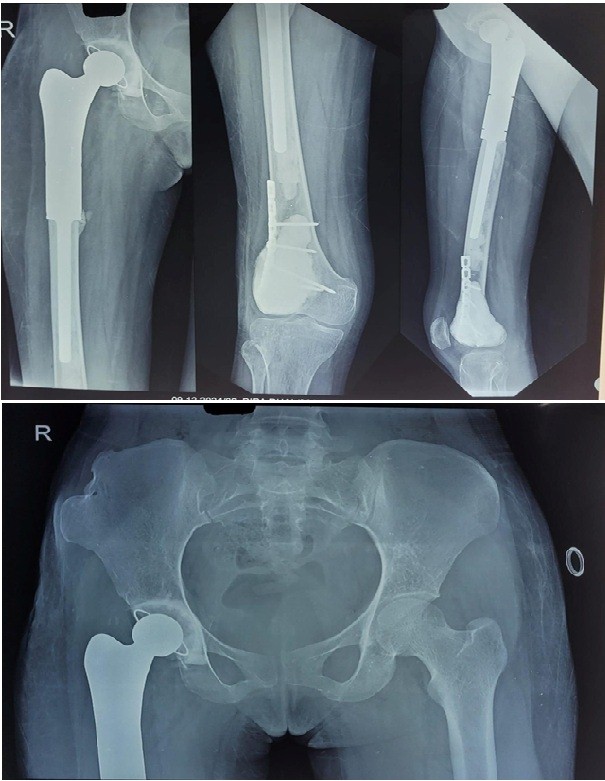

The proximal femoral GCT was excised and reconstructed using a proximal femoral mega prosthesis (Fig. 4).

Figure 4: Mega prosthesis of the proximal femur after excision of the tumor.

Figure 5: Curettage and bone cement filling of the distal femur skip lesion with supplementary fixation.

The distal femoral lesion was treated with curettage and bone cement filling (Fig. 5). In addition, a plate was applied at the distal femur for reinforcement. The patient was allowed to bear weight with a walker 21 days postoperatively. Gradually, she demonstrated significant clinical improvement, regaining the ability to bear weight without pain or support. A repeat HRCT of the chest showed regression of the small lesions. Postoperatively, denosumab was continued for 4 months as a monthly dose. Follow-up imaging over 12 months revealed no evidence of recurrence, and laboratory parameters remained within normal limits (Fig. 6).

Figure 6: 1-year follow-up of the case showing no recurrence with good fixation.